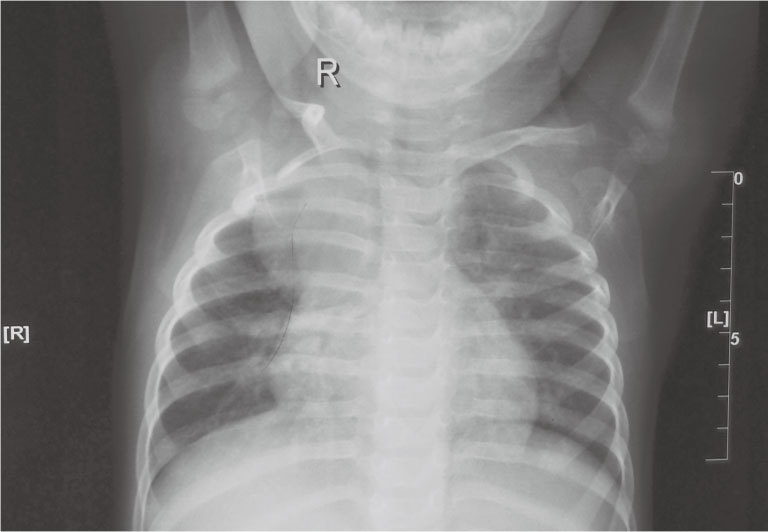

全組共有支氣管囊腫患兒12例,其中男9例,女3例,平均年齡17個月。術前均行正位胸部X線片、胸部B超、胸部增強CT掃描檢查,明確診斷縱隔內囊性包塊,包膜光滑完整,囊腔內密度均勻(圖 1~2)。其中囊腫占位偏于中線左側4例,右側8例,上縱隔9例,中縱隔3例。積極術前準備后行胸腔鏡手術治療。術后病理均為縱隔支氣管源性囊腫。